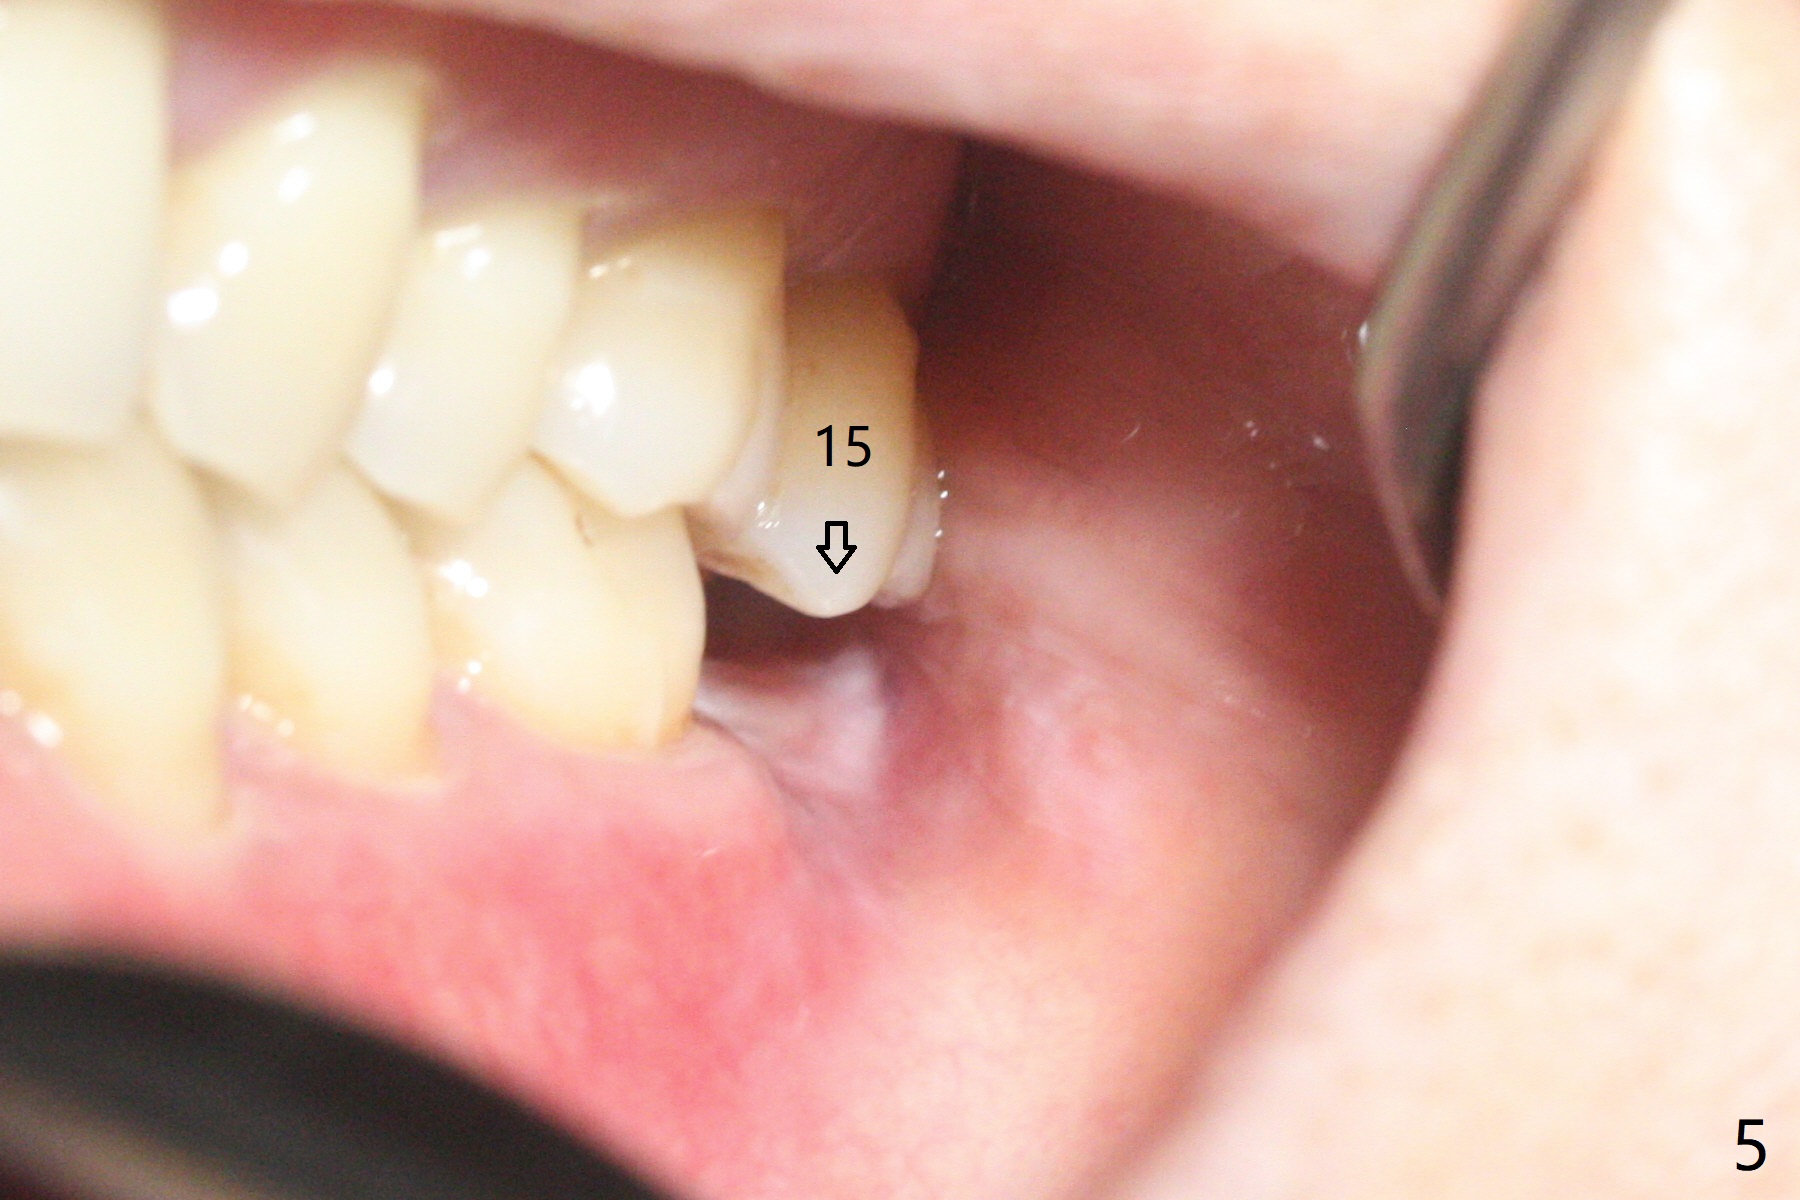

31号牙拔除前近中颊侧有一个瘘道(图一:<),说明32号牙被感染可能性小。术中发现虽然一小部分智齿牙冠与第二磨牙巨大牙槽窝相通(图二:*),但是病变并没有往智齿周围发展(S(可能是牙囊));借助导板(9毫米offset)毫无困难完成钻洞,但是嫌钻洞深度不够。由于植体扭力低(<10 Ncm),只好放置粘性骨粉(图三),覆盖PRF和Cytoplast,PTFE缝线,以及树脂敷料。病人左下第二磨牙缺失多年,牙槽嵴粘膜出现白色病变(图四:箭头),可能与对合磨牙延申有关(图五:箭头)。如果这个牙位需要导板植牙,垂直距离将是一个严峻问题。即种导板(图六:31)与延期导板(18)金属圈放置有不同,相差1.5毫米(图七):即种(由于拔牙)金属圈可以放低,而愈合牙位(由于牙龈存在)金属圈必须放高。所以第二磨牙即种有足够垂直空间优势。术后一周复诊,老的树脂敷料不牢(因为下面没有基台),脱落,下面不可吸收膜没有外翻,重新制作敷料(图八:A)。术后一个月由于2,3号牙之间牙周炎发作,树脂敷料牢靠,下面不可吸收膜稍微暴露,两者取出后,植体略微暴露。没有基台,骨粉固定好像不佳。